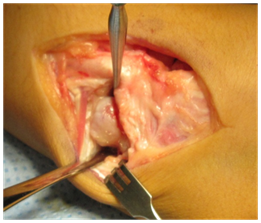

The surgery was done later on under general anaesthesia and with tourniquet control, the right wrist was approached dorsally with a longitudinal incision over the 4/5 extensor compartment, the capsule was opened with a ligament sparing technique, and a very large cartilaginous bone tumour, suggesting a osteochondroma, was found extended from dorsal to volar and to the ulnar side, sitting the main mass distal to the triangular fibrocartilaginous complex, where appeared to grow in a more round, smooth shape (Figure 3A-3D).

Figure 3A Ulnar side of the osteochondroma.

Figure 3B Removal of ulnar extension of the osteochondroma.

Figure 3C Piece showing the cartilaginous cover typical of the ostechondroma.

Figure 3D Seen clearly the distal portion of the TFCC undamaged.

A large tumour was removed measuring 2.0 cm for 1.5 cm and for 1.0 cm, and a second smaller one was also respected from the volar aspect of the lunate, trimming the fragment that was blocking the luno-capitate joint, that restoredthe ulnocarpal space distal to the TFCC and at the same time improved the wrist motion at the midcarpal joint.